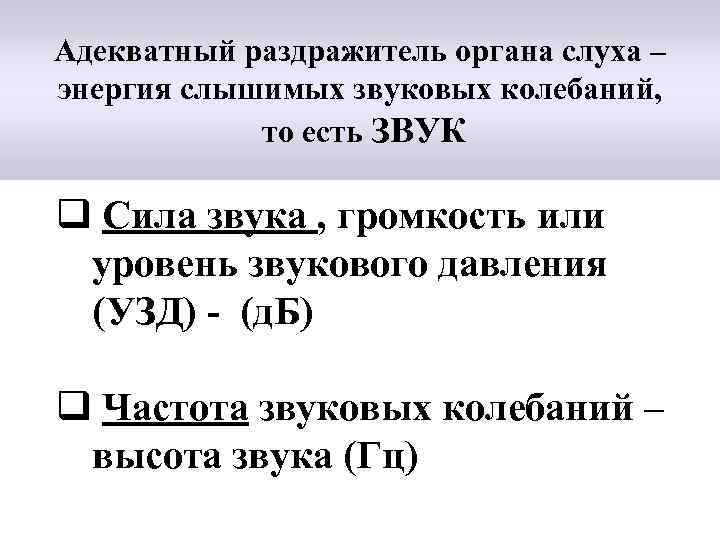

Адекватный раздражитель органа слуха – энергия слышимых звуковых колебаний, то есть ЗВУК q Сила звука , громкость или уровень звукового давления (УЗД) - (д. Б) q Частота звуковых колебаний – высота звука (Гц)